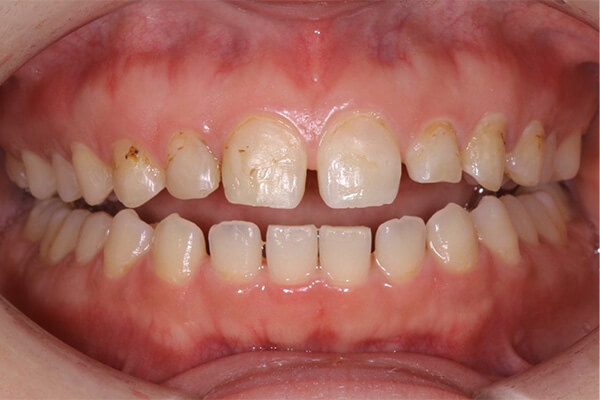

- After

上の前歯の被せ物が長い期間保つようにするためには、下の前歯のガタガタを整えておく必要があります。この症例くらいのガタガタであれば、インビザラインGoを使えば短期間で綺麗に治すことができます。歯並びが整ったことで治療のモチベーションが上がり、ホワイトニングと奥歯の銀歯を全てセラミックに置き換える治療を行い、金属がない(ノンメタル)状態になりました。